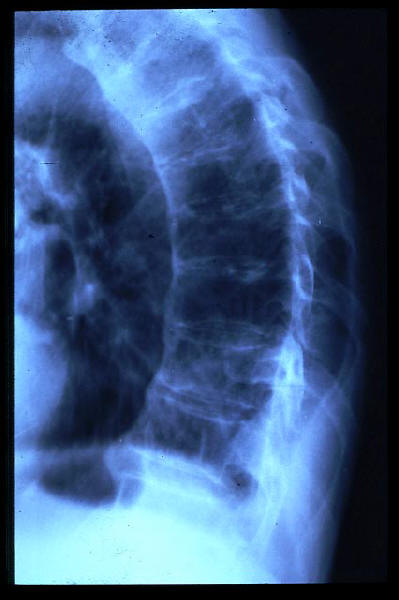

Paquipleuritis. Fractura costal.